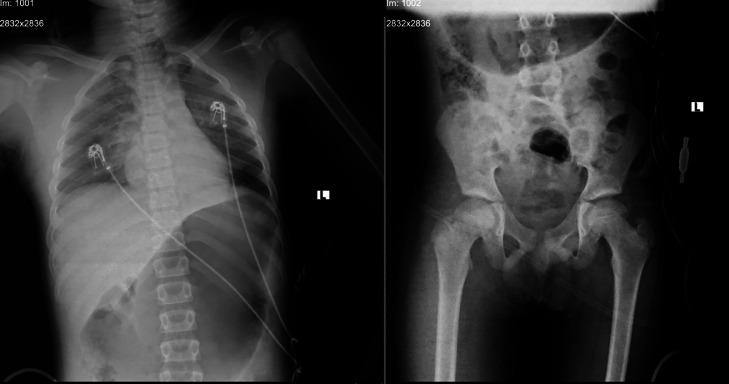

小儿绞缢伤:快速干预与神经功能完全恢复

Pediatric hanging injury: Rapid intervention and full neurological recovery.

Hanging injuries are a subset of strangulation injuries that pose significant risks of hypoxia and neurological damage, especially in pediatric populations. This report presents a case of a 13-year-old boy with hypoxic brain injury following a suicide attempt by hanging. Key aspects include the prolonged duration of strangulation, absence of vertebral or laryngeal trauma, successful intensive care management, and full recovery without residual neurological deficits. This case emphasizes the importance of timely intervention, multidisciplinary management, and preventive education to address the acute and long-term challenges of pediatric hanging injuries.

悬吊伤是绞窄伤的一种,具有显著的缺氧和神经损伤风险,在儿童群体中尤为如此。本报告介绍了一例13岁男孩在试图上吊自杀后出现缺氧性脑损伤的病例。关键要点包括绞窄时间延长、无脊椎或喉部创伤、成功的重症监护管理以及完全康复且无残留神经功能缺损。该病例强调了及时干预、多学科管理和预防教育对于应对儿童悬吊伤的急性和长期挑战的重要性。